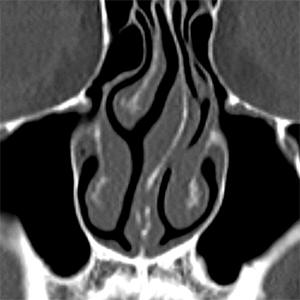

左:鼻中隔軟骨の骨折 右:篩骨正中板の湾曲

上:鼻中隔軟骨の骨折 下:篩骨正中板の湾曲

機能面では鼻づまりの症状があり、CTで鼻中隔の曲がりを認め、一部外傷によると思われる中隔軟骨の骨折もありました。